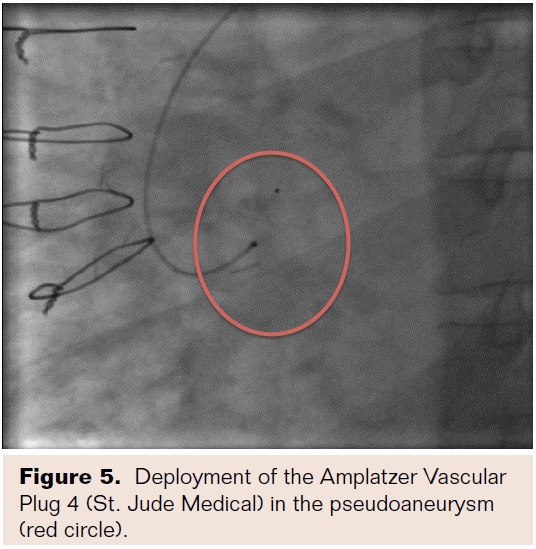

The glidewire was removed and a 6 mm Amplatzer Vascular Plug 4 (VP4; St. Jude Medical) was advanced through the DAC catheter and half of the device was exposed in the PSA. The device was pulled back so that the second dome was exposed on the aortic side (Figure 5). Aortography was performed to demonstrate occlusion and the device was assessed for stability. Once stability and closure were confirmed, the device was released. Repeat aortography revealed no residual leak (Figure 6). There were no complications of the procedure and the patient did well post-procedure. This patient received standard post aortic dissection follow-up with CT angiogram at discharge, CT angiogram 1 month after discharge, and then subsequent yearly CT angiograms. No subsequent bloodwork was performed.